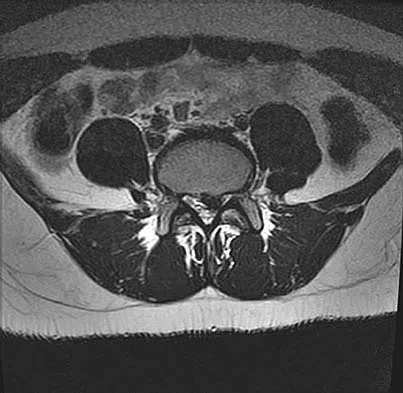

A 50-year-old man with no history of trauma reports new-onset back pain after doing some yard work the previous day. He reports pain radiating down his leg posteriorly and into the first dorsal web space of his foot. MRI scans are shown in Figures 3a through 3c. What nerve root is affected?

Detailed Explanation